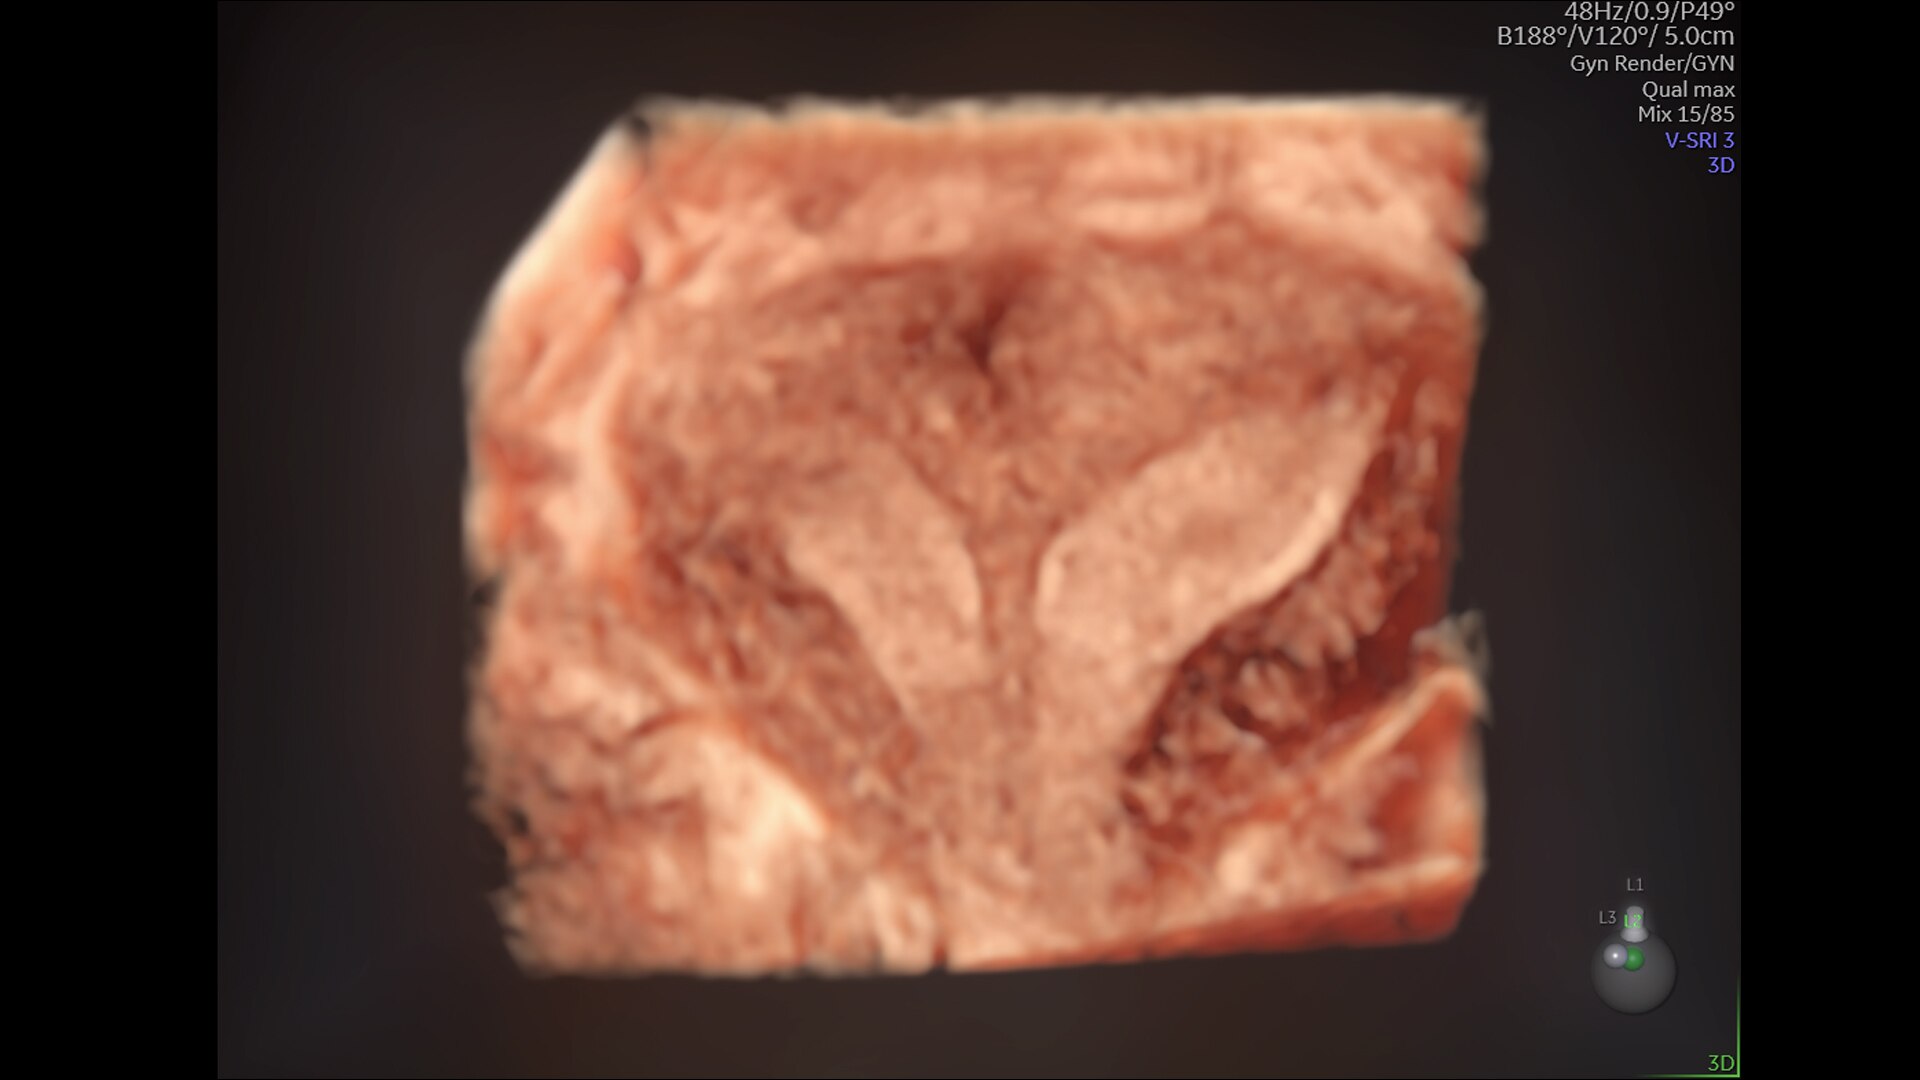

Enhanced Volume Imaging

Deliver next generation 3D/4D & Color images with HDlive Studio+